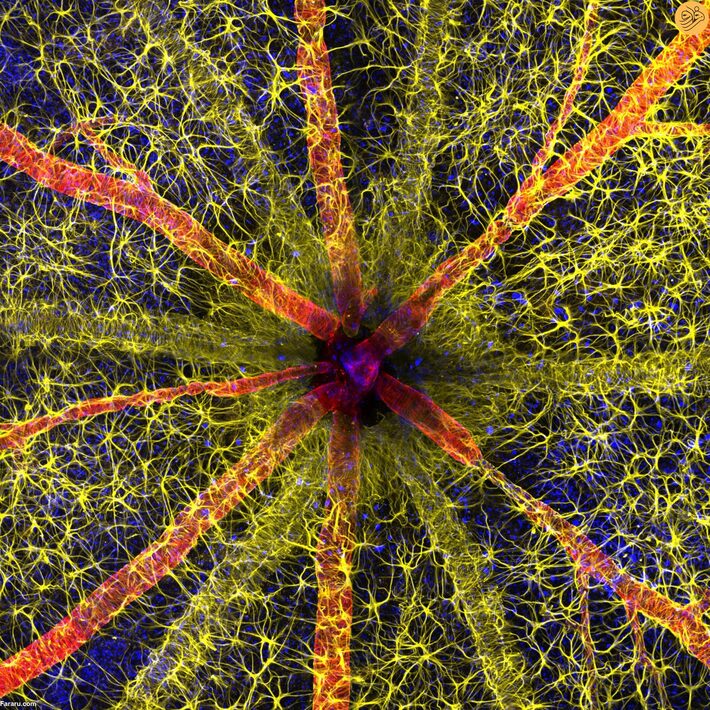

چهل و نهمین مسابقه سالانه عکاسی میکرو یا عکاسی جهان کوچک نیکون برندگان خود را اعلام کرد و جایزه برتر به حسنین قمبری برای تصویر واضح او از سر عصب بینایی یک جونده تعلق گرفت.

عکس برنده که توسط قمبری و با کمک جیدن دیکسون از موسسه the Lions Eye گرفته شده، جزئیات بسیار زیادی از جمله آستروسیتها (زرد)، پروتئینهای انقباضی (قرمز) و عروق شبکیه (سبز) را از داخل سر عصب بینایی نشان میدهد.

نیکون خاطرنشان کرده که این عکس، فقط یک تصویر رنگی زیبا نیست، بلکه کمک مهمی به مطالعه آسیب شبکیه در نتیجه دیابت کنترل نشده یا رتینوپاتی دیابتی میکند. از هر پنج فرد مبتلا به دیابت در سراسر جهان، یک نفر این مشکل را دارد.

رتینوپاتی دیابتی زمانی رخ میدهد که قند خون بالا به رگهای خونی در بافت پشت چشم، معروف به شبکیه آسیب میرساند. رگهای خونی آسیب دیده متورم شوند و نشت میکنند و رگهای نابجایی هم ایجاد میشود که مجچموع اینها میتواند باعث تاری دید یا از دست دادن کامل بینایی شود. نیکون توضیح داده که از سال ۲۰۲۱، قمبری زمان و تحقیقات خود را صرف تشخیص زودهنگام و معکوس کردن این بیماری کرده است.